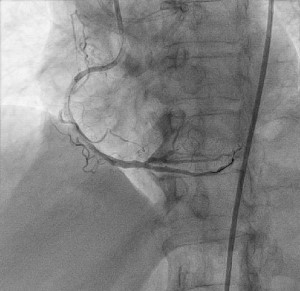

Una paciente de 80 años con antecedentes de diabetes mellitus tipo 2, hipertensión arterial, dislipidemia y cáncer de mama hace 6 años (con requerimiento de radioterapia) ingresó al hospital por dolor torácico de características típicas. En el examen físico se encontraron signos vitales estables, no hubo dificultad respiratoria ni tampoco signos de congestión pulmonar o sistémica. Se tomaron biomarcadores y un electrocardiograma, y los resultados fueron negativos para isquemia aguda. El ecocardiograma mostró fracción de eyección del ventrículo izquierdo (FEVI) conservada, dilatación auricular izquierda, ausencia de trastornos de la contractilidad e insuficiencia mitral leve a moderada. La coronariografía evidenció arteria coronaria izquierda sin lesiones obstructivas significativas, lesión calcificada del 70 % en el tercio proximal de la arteria descendente anterior y del 70 % de tercio medio de la misma arteria, coronaria derecha ocluida totalmente en su tercio medio, vaso severamente calcificado y oclusión total de la arteria posterolateral. Además, se realizó el diagnóstico de enfermedad coronaria multivaso; se solicitó la valoración por cirugía cardiovascular, que indicó que no había posibilidad de realizar el procedimiento quirúrgico por calcificación a lo largo de todas las arterias coronarias. Posteriormente, se llevó a cabo una coronariografía, donde se realizó la permeabilización de descendente anterior y posterior por medio de la AR e insertaron un estent medicado (Figura 1 y Figura 2). Durante el procedimiento, se reportó la microperforación de la arteria posterolateral, pero fue posible corregirla en el mismo tiempo quirúrgico con la técnica de embolización con micropartículas. Luego de la intervención, la paciente tuvo una adecuada evolución clínica y se dio su egreso.